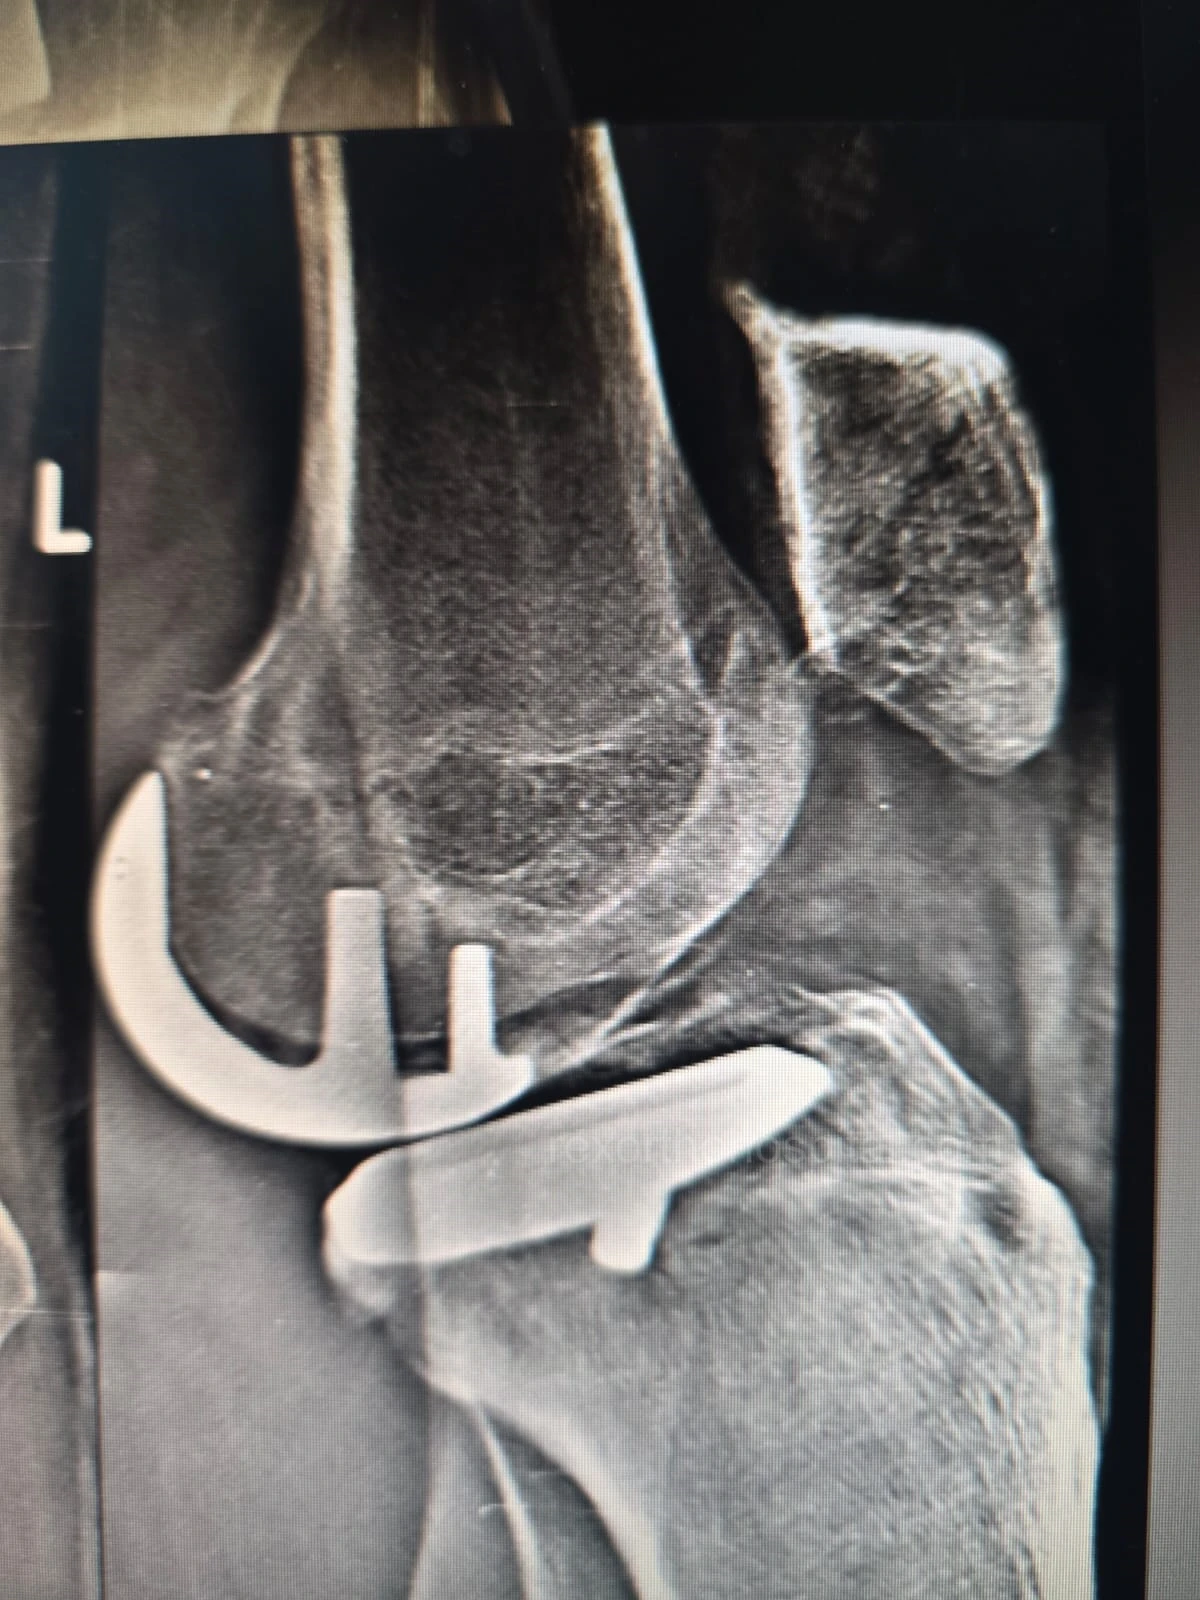

Elbow stiffness treatment aims to restore smooth movement and reduce pain caused by injury, arthritis, or long-term immobility. Our approach improves flexibility and helps regain everyday function.

From diagnosis to surgery and recovery, our team ensures you receive expert treatment and individual attention throughout your treatment journey